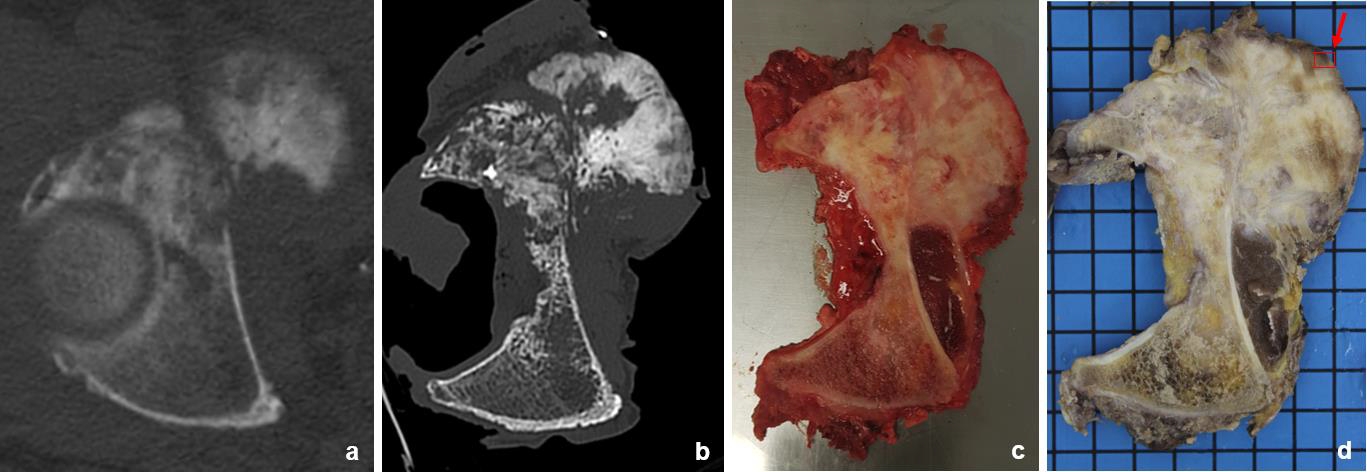

**Vergleichende Visualisierung des axialen Schnittes mit der kritischen Tumorausdehnung ins kleine Becken im (a) präoperativen CT, (b) im hochaufgelösten postoperativen CT des Tumorpräparates (daher ohne Oberschenkelkopf), (c) der unfixierte axiale Knochenschnitt mittels Gewebesäge und schließlich (d) dieser Knochenschnitt nach Fixation in Formalin mit Fotodokumentation in der Pathologie (Ltd. OÄ PD Dr. med. K. Specht, Institut für Allg. Pathologie und Pathologische Anatomie der TUM) und anschließender flächendeckender histologischer Aufarbeitung des Präparates nach Entkalkung mit genauer räumlicher Zuordnung.